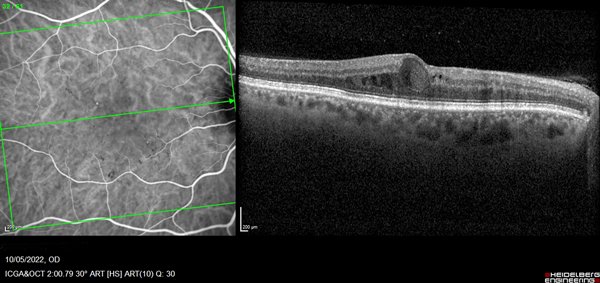

Optical coherence tomography (OCT Spectralis® HRA, Heidelberg Engineering Inc, Germany) scan showed intraretinal oval accumulations of fluid with increased OCT signal intensity corresponded to regions of SSPiM structures in the outer nuclear layer, adjacent to the outer plexiform layer. Cross-sectional flow signal overlaid OCT scans showed that these structures had highly prominent flow signals that were clearly different from projection artifact signals originating in the vasculature of inner retinal layers (Fig. 1).

Figure 1. OCT showed in right eye an intraretinal cyst with hyperreflective fluid in HFL and is bordered by hyperreflective materials.